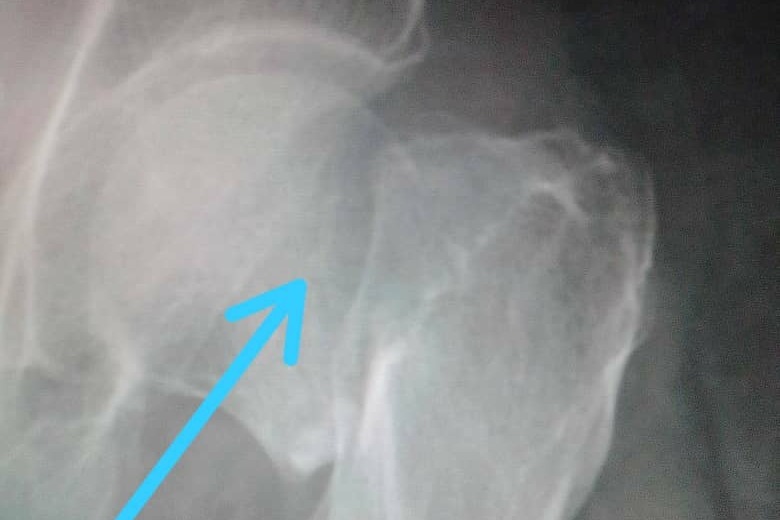

Beatriz del Carmen Fernandez De La Paz, 85 years young, fell and fractured her left femur on Sunday afternoon, December 26, 2020 as she arose from a nap. Her grandchildren rushed Beatriz to the Central Hospital of Maracay in Venezuela, the largest public hospital in the region, where she was denied care because the hospital lacks beds and patient care is backlogged for 2 months. Fortunately, Orthopedist, Dr. Carlos A. Hernandez C., of the private clinic Centro Medico, Maracay was able to see and evaluate her. Dr. Hernandez C. determined that Beatriz requires a prosthetic hip replacement surgery. Please see the attached documents with the doctor’s diagnosis, the x-rays, and the cost estimates for the prosthetic and procedure.

En la tarde del domingo 26 de diciembre del 2020 al levantarse de una siesta Beatriz del Carmen Fernández De La Paz, de 85 años de edad, sufrio una caida donde se fracturó el fémur del lado izquierdo de su cadera. Sus nietos la llevaron al Hospital Central de Maracay en Venezuela, el hospital público más grande de la región, donde se le negó la atención debido a que el hospital carece de camas y la atención de los pacientes está atrasada durante 2 meses. Afortunadamente, el ortopedista, Dr. Carlos A. Hernandez C., de la clínica privada Centro Médico, Maracay pudo atenderla y evaluarla. El Dr. Hernandez C. determinó que Beatriz requiere una cirugía de reemplazo de cadera prostética (Protesis de Cadera de Thompson) Adjuntos encontraran el diagnóstico del médico, las radiografías y las estimaciones de costos de la prótesis y el procedimiento a seguir.